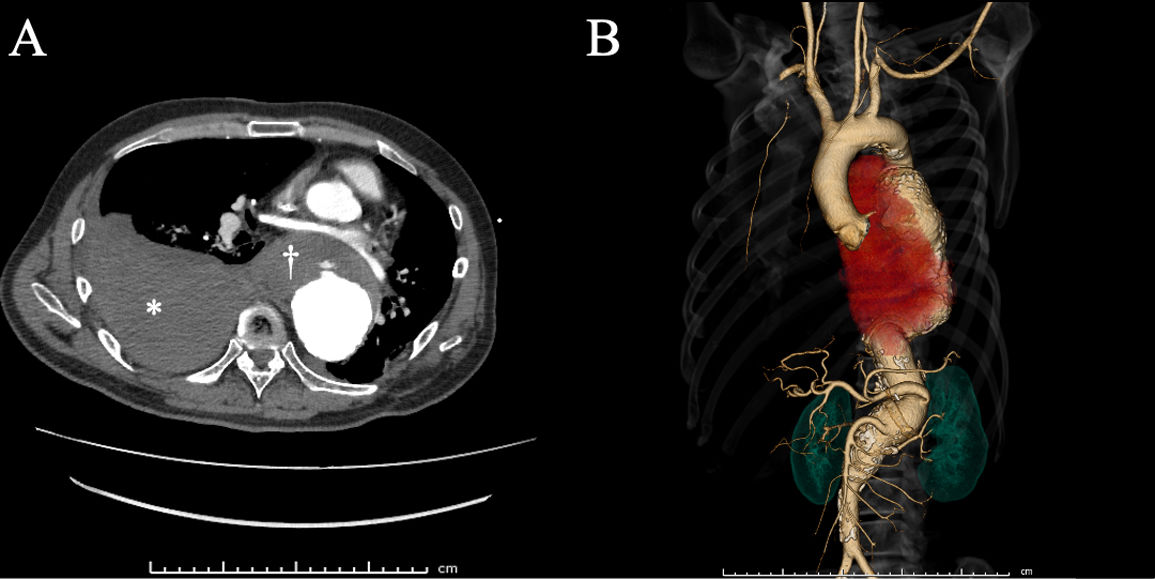

Right hemothorax due to a ruptured descending thoracic aortic aneurysm

Hemotórax direito devido a rutura de aneurisma da aorta torácica descendente